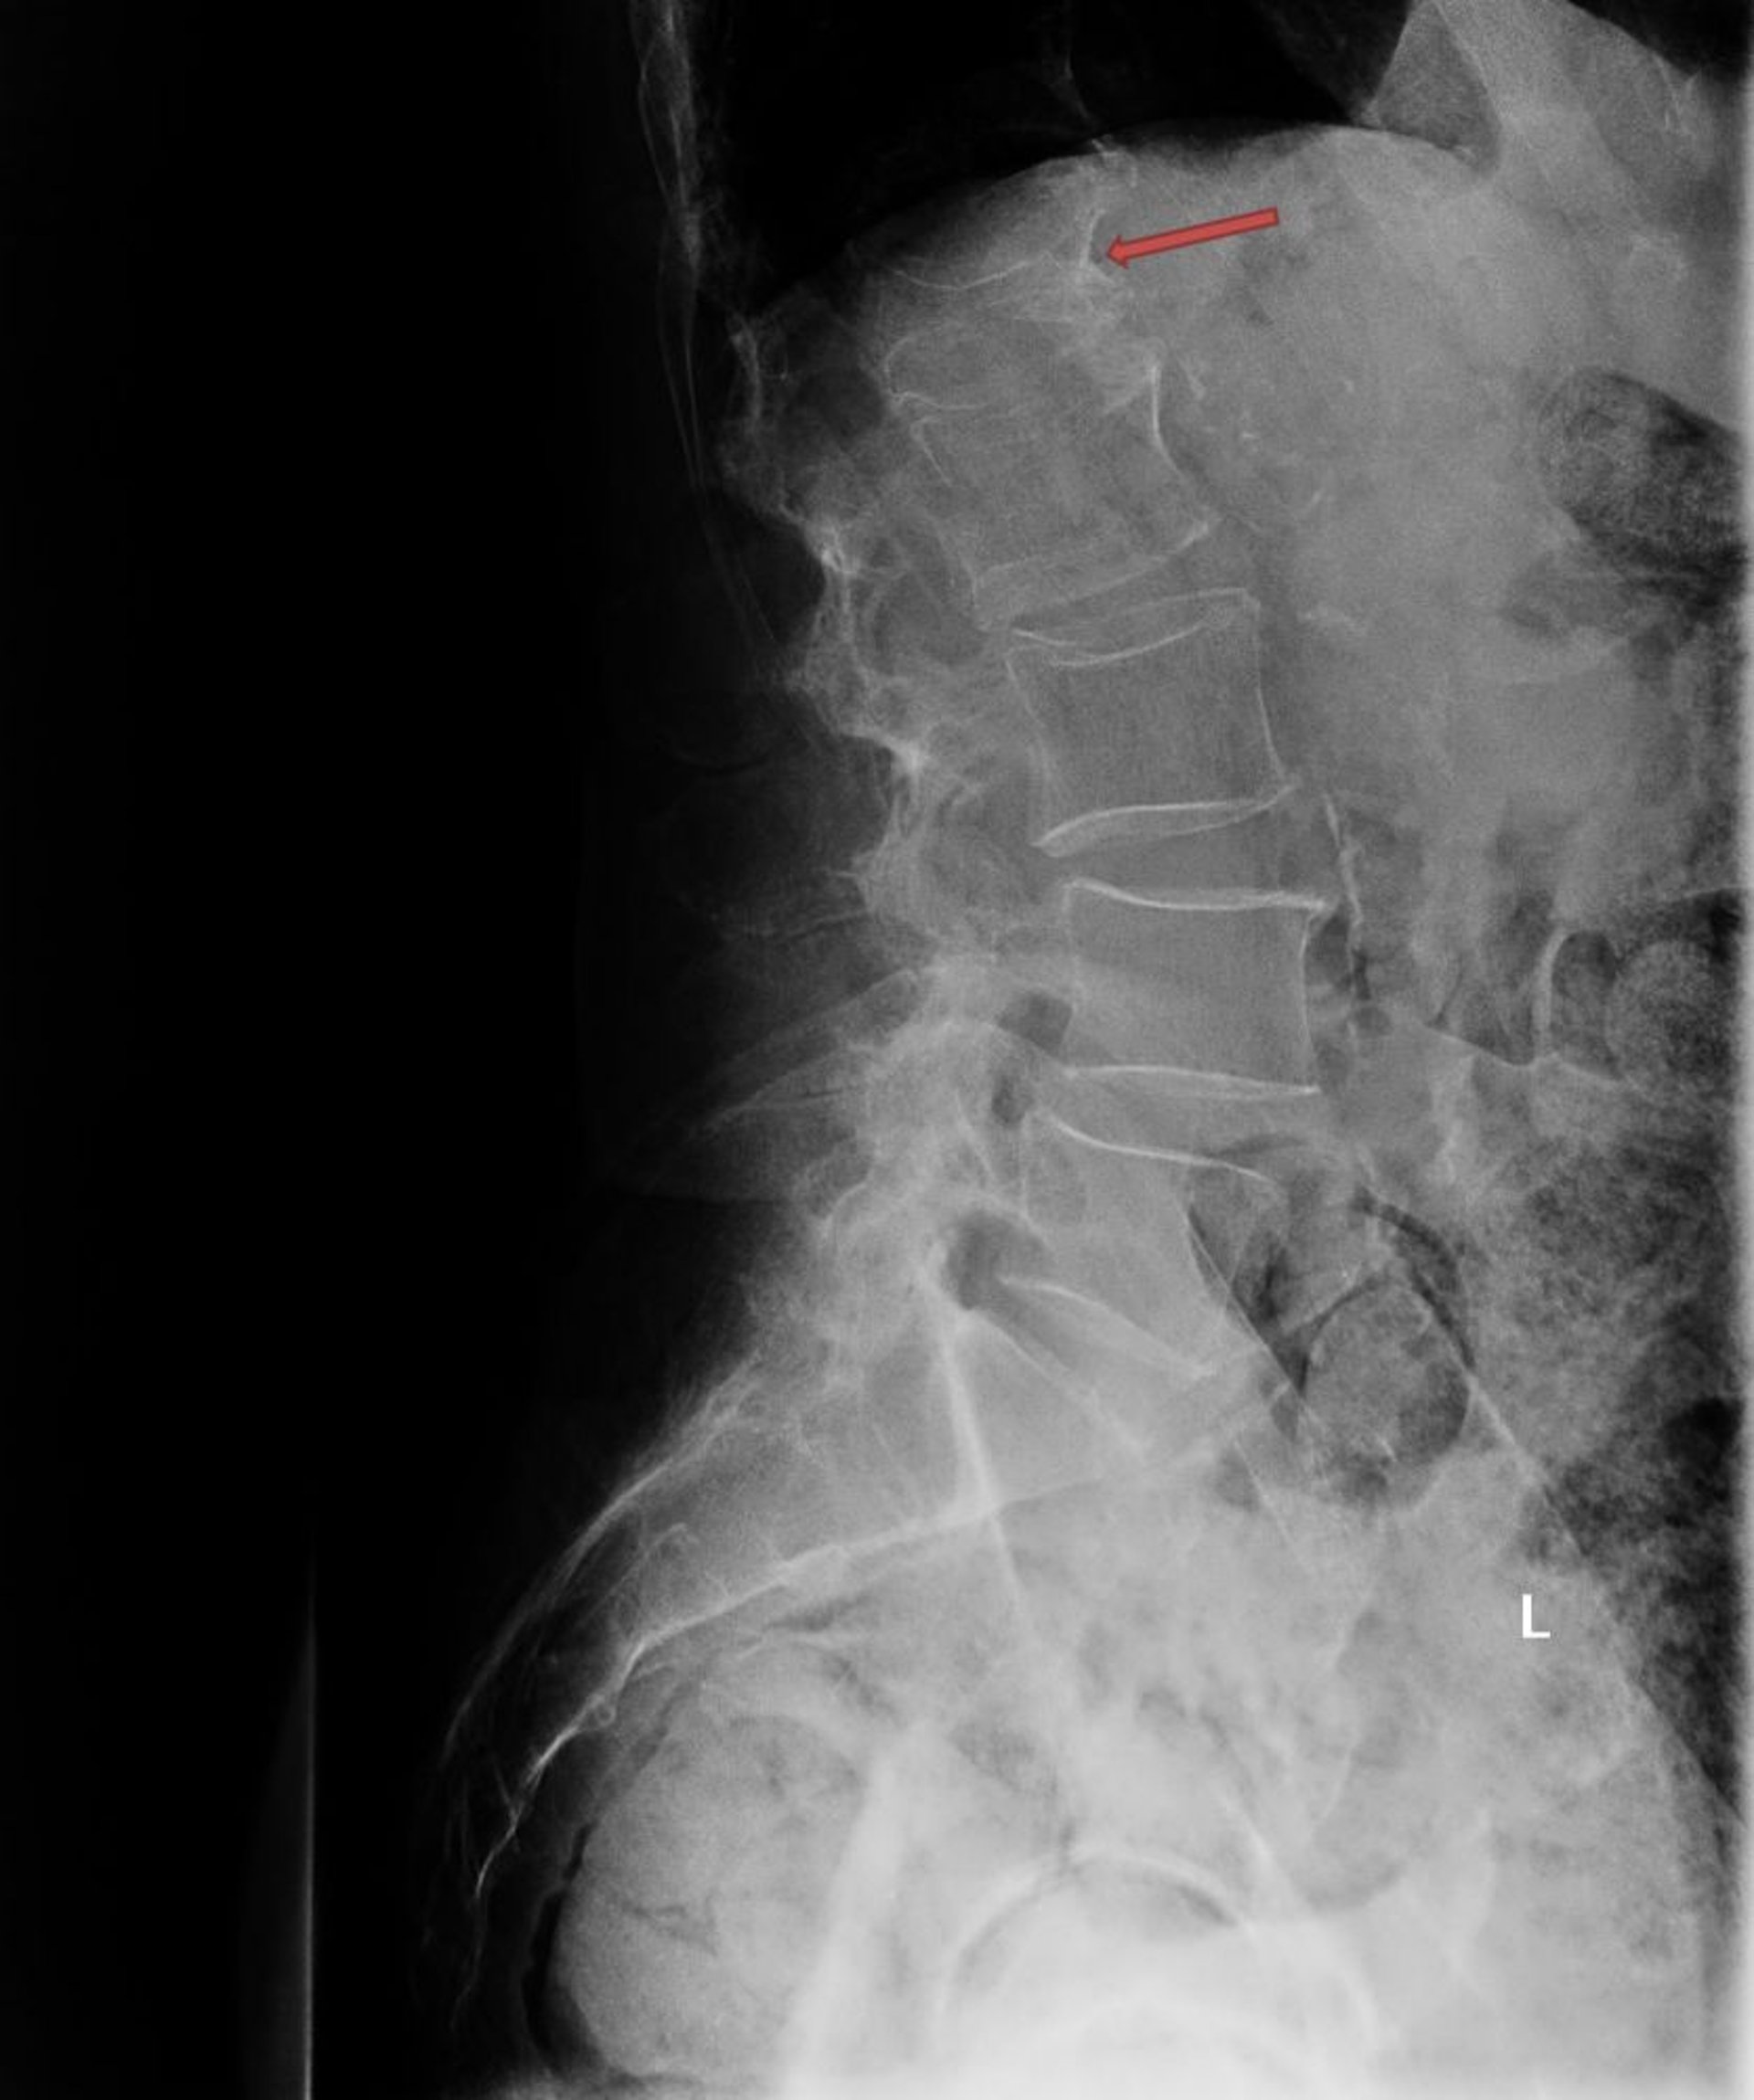

Esta radiografía muestra una fractura por compresión osteoporótica grave de la primera vértebra lumbar (L1; flecha).

Photo courtesy of Marcy B. Bolster, MD.